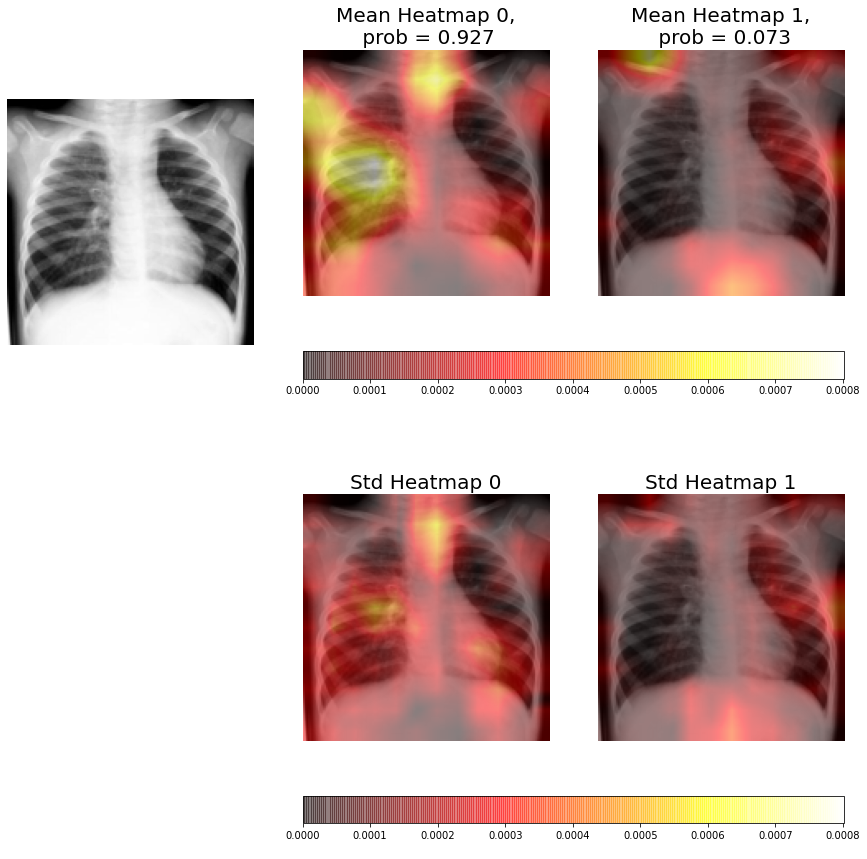

The ensembles are composed by five individual CNNs, therefore, for each radiography we have five different heatmaps for each class (consolidation / non-consolidation). This allows us to compute the average heatmap and the uncertainty at each pixel (standard deviation at each pixel) for each class.

In Figures 9-11 we can see from left to right, and from top to bottom, the original X-ray, the average heatmap for the "non-consolidation" class, the average heatmap for the "consolidation" class, and the standard deviation heatmaps.

This visual representation provides to medical staff with relevant information. Firstly, the probabilities of each class predicted by the model are shown in the title of each average heatmap. Secondly, the average heatmaps show the areas of the X-rays that are most informative according to the ensemble. Finally, the standard deviation heatmaps provide information about the areas of greatest disagreement among individual CNNs (that is, the areas with the greatest uncertainty). This suggests that medical staff should pay more attention to areas with higher values in the average heatmaps and in the standard deviation heatmaps.

In Figure 9 we can see that the average heatmap for neuron 0 (non-consolidation class) is much brighter than the average heatmap for neuron 1 (consolidation). If we compare this visualization with the one obtained by an individual CNN (Figure 6), we can see that it analyzes left lung in greater depth than the stand alone model, and focuses on the most relevant features to perform the X-ray classification. It also has a low standard deviation in this area and, unlike the visualization obtained by the individual CNN, it is hardly fixed on the heart area. Therefore, it can be concluded that the ensemble result is better than the one obtained by the individual CNN.